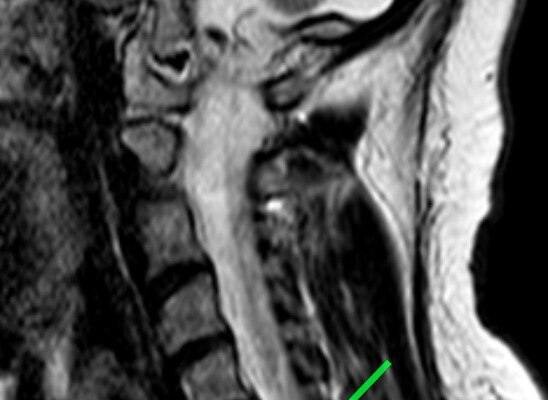

Пациентка обратилась с жлобами на изматывающую боль в руке. Ей провели МРТ, которое показало, что в шейном отделе сформировалась грыжа размером 8 мм. По словам медиков, образование сдавливало спинномозговой канал и корешковое отверстие, угрожая двигательной функции.